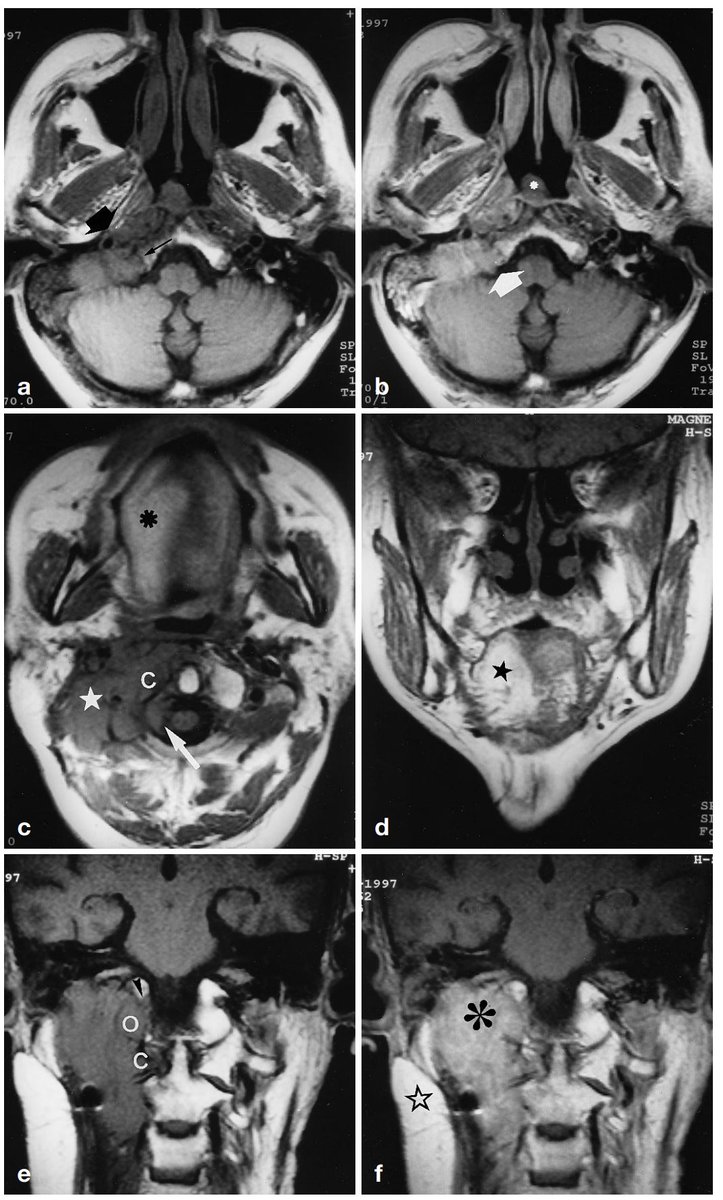

Normal on the right vs. mucoepidermoid carcinoma from left parotid

Actually, bonus fact:

The auriculotemporal nerve is a potential connection between CN V3 and VII for perineural spread. Look just posterior to the mandible!

http://ajnr.org/content/23/2/303